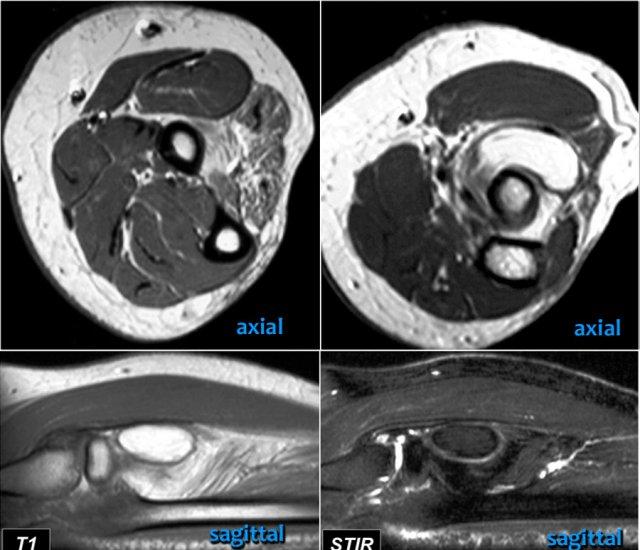

Tear of distal biceps tendon

Có một vết rách hoàn toàn, vì nếu chúng ta theo dõi gân đến tận củ quay, chúng ta có thể thấy rằng gân không bám vào đó (mũi tên xanh lá).

Chỉ có dịch.

Lý do tại sao gân không bị co rút là vì cân cơ nhị đầu rộng – còn được gọi là lacertus fibrosus – vẫn còn nguyên vẹn (mũi tên đỏ).

Gân nhị đầu xa không chỉ bám vào lồi củ xương quay, mà còn thông qua lacertus fibrosus bám vào cân cơ của khối cơ gấp-sấp ở phía trong cẳng tay.

Gân xa của cơ nhị đầu được khoanh tròn ở hình ảnh phía trên bên trái.

Khi cân cơ cũng bị rách, thì gân sẽ co rút lại và bạn sẽ thấy một khối phồng rõ ràng ở cánh tay do cơ nhị đầu bị co lại.